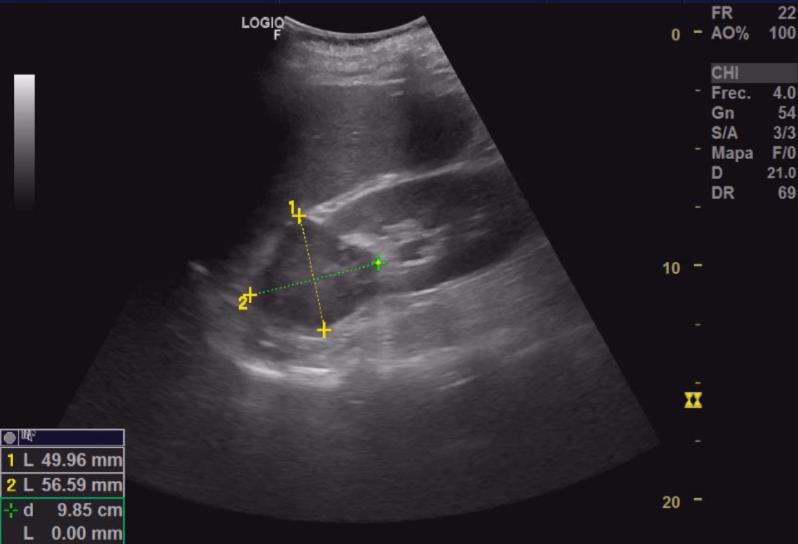

Importante colección anecoica supradiafragmática compatible con derrame pleural masivo (2/3 pulmón derecho), con flóculos ecogénicos (tongue-like sign) sugerentes de parénquima pulmonar atelectásico. Escasa colección anecoica pericárdica. Se identifica en riñón izquierdo una imagen heterogénea de bordes bien definidos en polo superior invadiendo pelvis, de unos 52x58x60 mm, con aumento de captación doppler.Pruebas complementarias